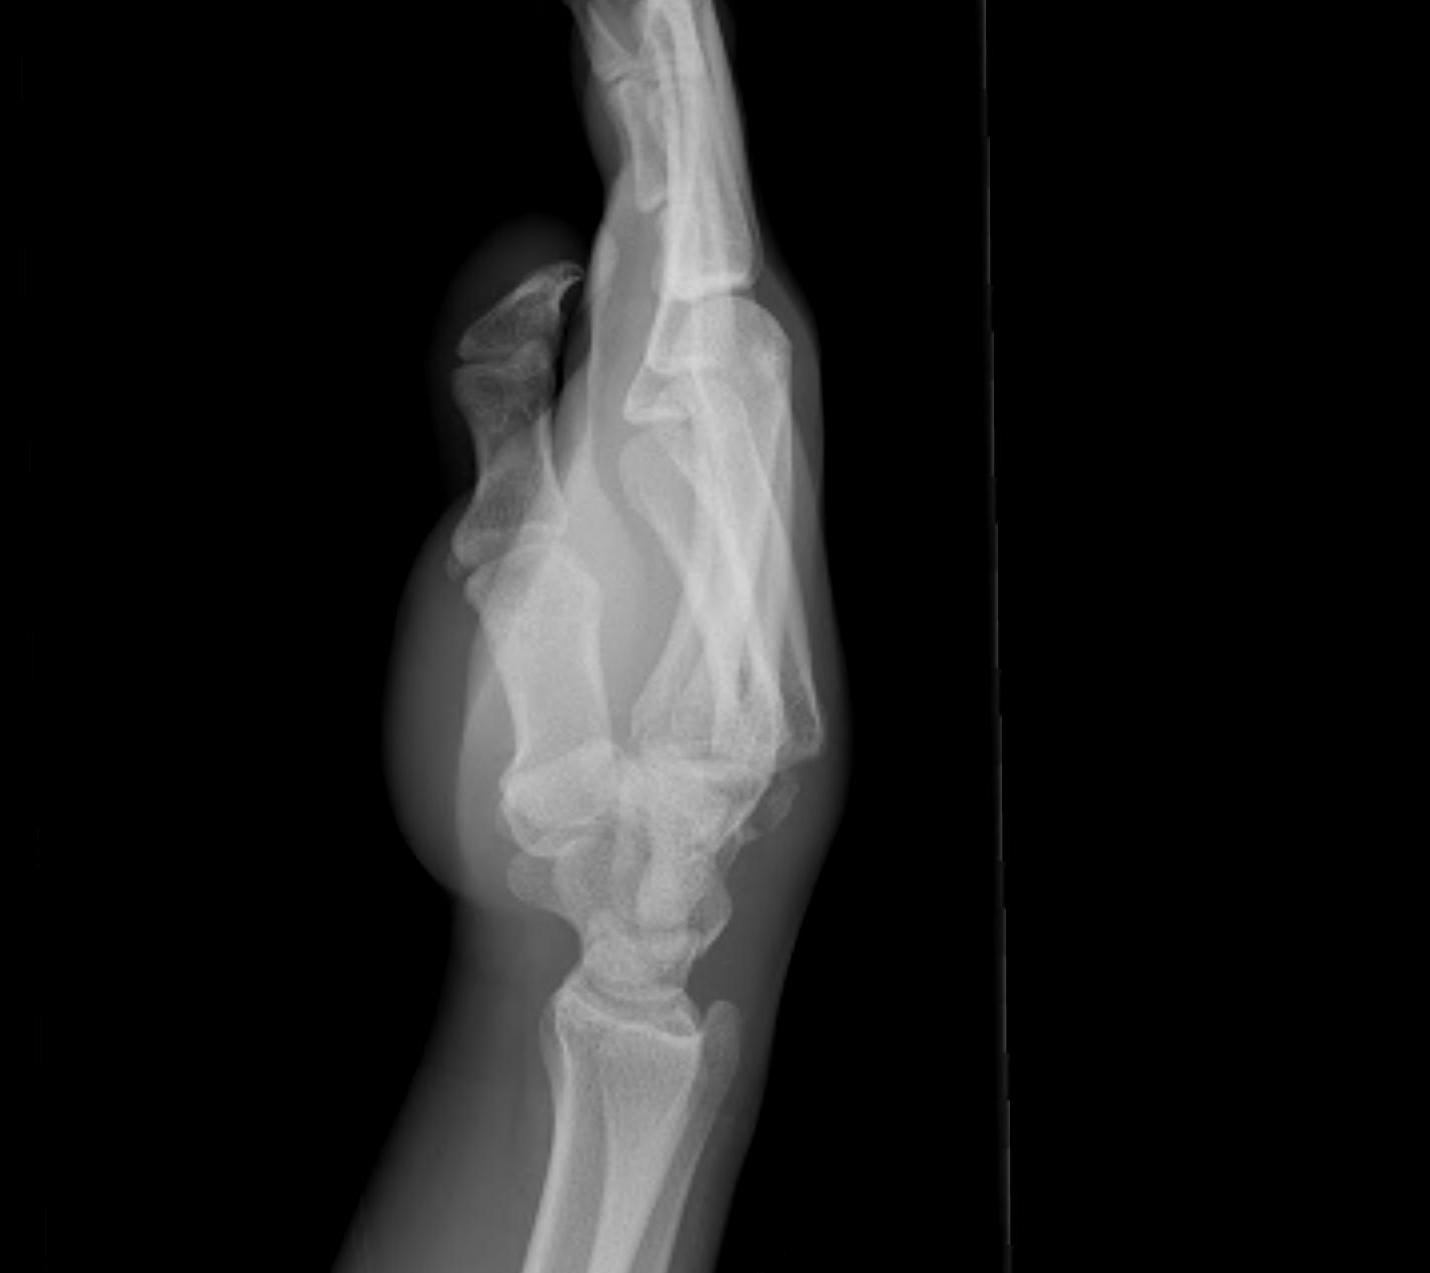

5. MCPJ Dislocation

Simple

- volar plate not interposed

Complex

- volar plate, lumbricals, flexor tendons interposed

- open reduction